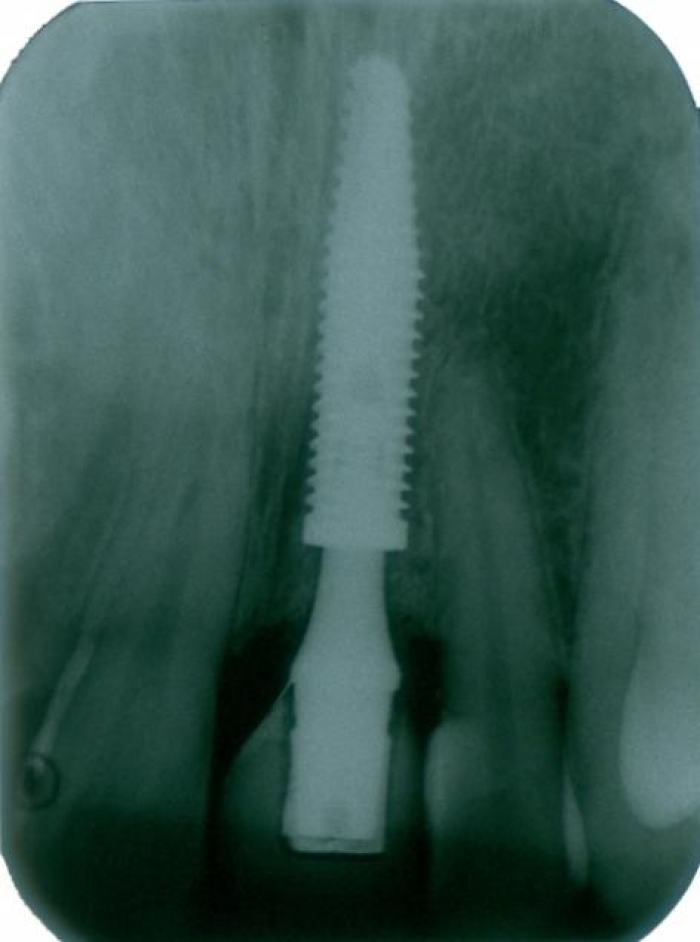

Imagem do implante instalado, com provisório imediato